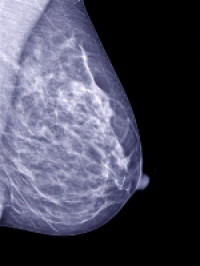

Because screening mammography has been well-accepted in the United States, the researchers forecast rising numbers of both invasive and in-situ tumour diagnoses, which are almost entirely detected via screening mammography.